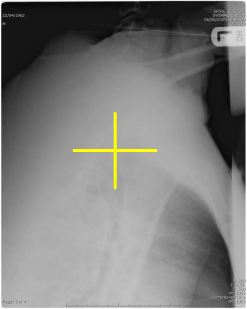

Evaluate the Lateral C-spine radiograph below and select any of the statements that are true (multiple answers possible):

All required vertebrae are demonstrated

A repeat with more flexion of the head/neck is needed

The R/L marker is correct

This is a well-positioned radiograph; no repeat required.

3 only